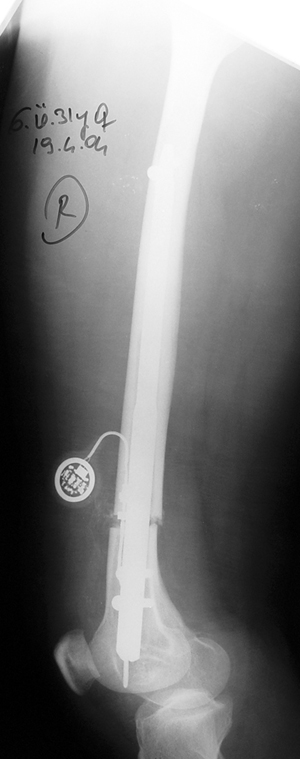

Since 2005 Dr. Mehmet KOCAOGLU is the first most Fitbone operating surgeon in TURKEY. He established the center of excellence for Fitbone surgeries in Istanbul. Fitbone comprises a telescopic nail implant that can extend, powered by an electric motor and controlled by a receiver with an antenna that is buried under the skin; the receiver in turn is controlled by a hand-held radio-frequency transmitter. The procedure for lengthening the lower leg is as follows:

A two-centimetre incision is made at the patient’s knee, and a rimmer is used to create enough space in the bone for a stainless steel nail.

The bone is cut about 14 cm below the knee from the inside with an internal saw. The stainless steel nail is held in place by two screws. The top of the nail is attached to a tiny, plastic-encased receiver that is placed under the skin. The patient controls the lengthening process. By pushing a button on the transmitter when it is placed against the antenna, the built-in motor extends the nail one millimetre per day. When the leg has grown to the desired length, lengthening stops, and the bone is allowed to solidify. The device can be removed about two years after the initial surgery. This procedure, however, comes at a price. While the Ilizarov external fixator costs approximately USD$4,000, and the ISKD implant about USD$8,000, the Fitbone device carries a price tag of roughly USD$15,000 (all prices exclusive of surgery costs).